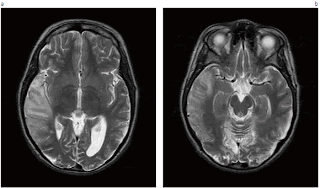

Se han identificado al menos 10 mutaciones diferentes, pero el 80 % de los casos se deben a la mutación 3243A> G en el gen del ARNt de leucina. Así pues, se suele mencionar esta mutación con el nombre de mutación de MELAS a pesar de su asociación con diversos cuadros clínicos: su prevalencia en la población general en Europa se ha estimado en 1/6 250. La mutación 3271T> C del gen ARNt Leu se asocia con el síndrome en un 7,5 % de los pacientes. El diagnóstico del síndrome MELAS se basa en el cuadro clínico y en la resonancia magnética nuclear cerebral.

La RM puede revelar muchas lesiones hiperintensas en T2 en sustancia cerebral gris y blanca, mientras que la tomografía computarizada muestra atrofia cerebral y calcificación de los ganglios basales. En ellas se observa que las lesiones no se limitan a los territorios vasculares y por lo tanto que los episodios agudos no son apoplejías típicas. La acumulación anómala de lactato en sangre es frecuente y casi constante en el líquido cefalorraquídeo. La biopsia muscular es anómala en aproximadamente el 85 % de los pacientes. Elanálisis de la actividad de la cadena respiratoria muscular puede revelar una deficiencia del complejo I o una deficiencia combinada de los complejos I y IV.